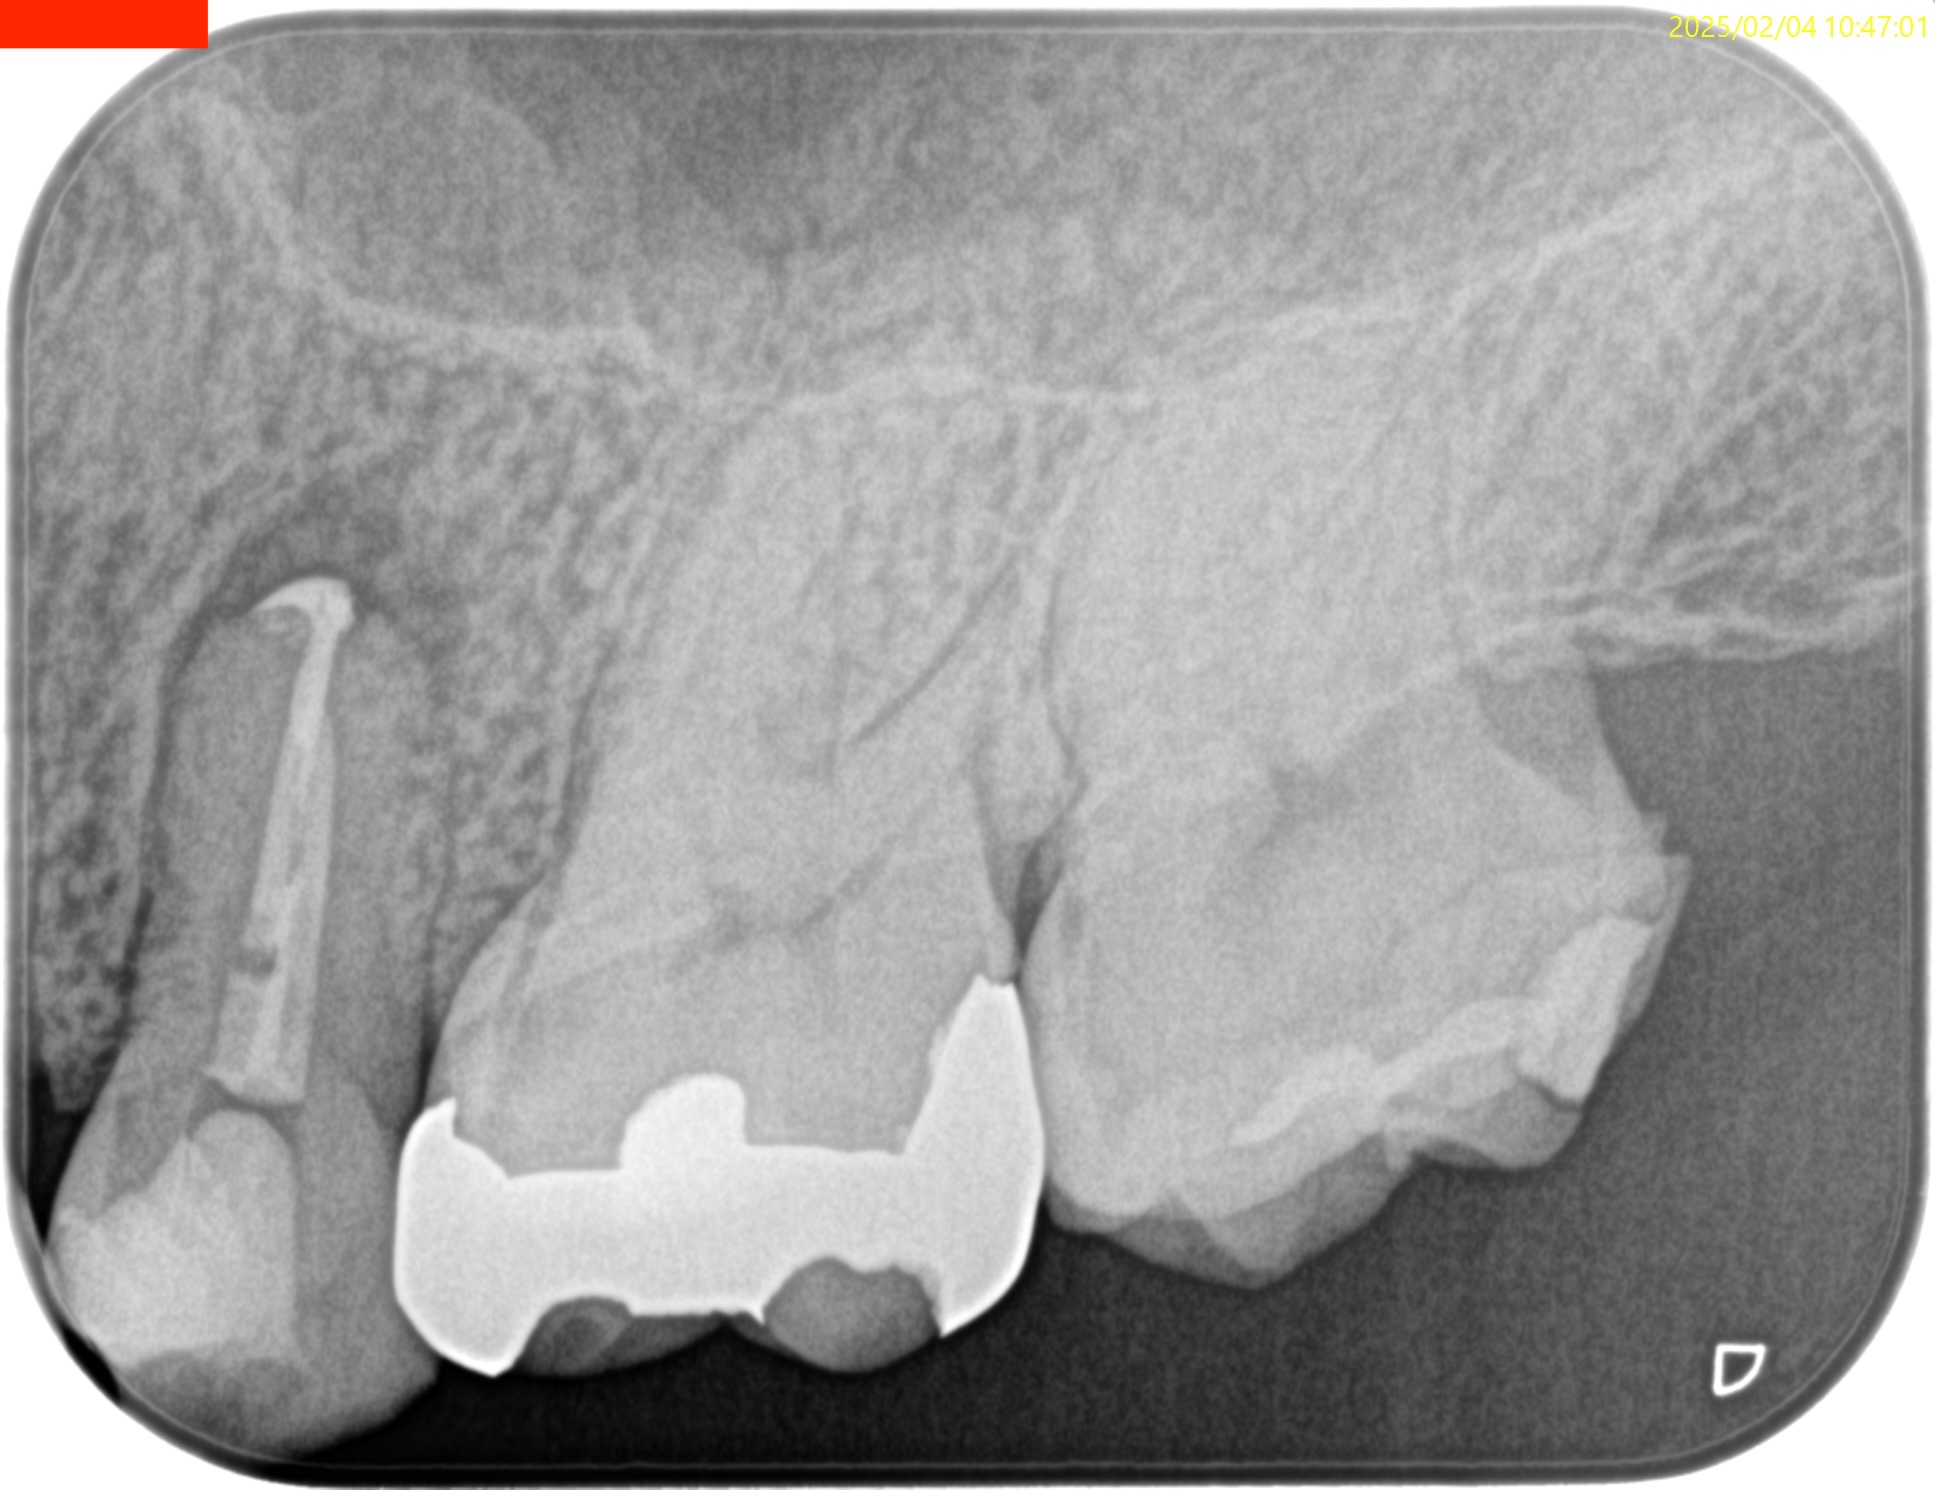

合流地点を確認し以下のように根管形成して

術後にPA, CBCTを撮影した。

B

P